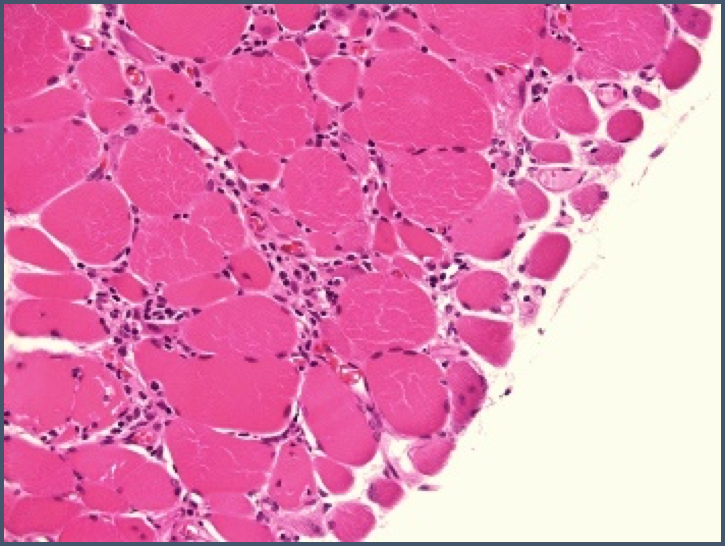

What myopathic change is this?

Perifasicular atrophy